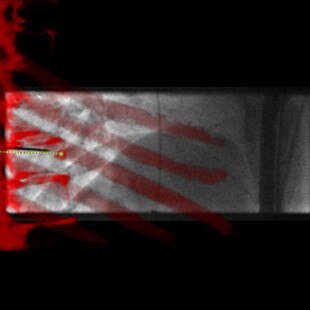

INTERVENTIONS AU NIVEAU DU RACHIS